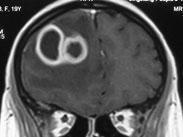

耳源性腦膿腫

• 耳源性腦膿腫

628健康網為您分享有關耳源性腦膿腫的癥狀,耳源性腦膿腫的治療方法,耳源性腦膿腫的預防知識,耳源性腦膿腫的癥狀圖片,耳...